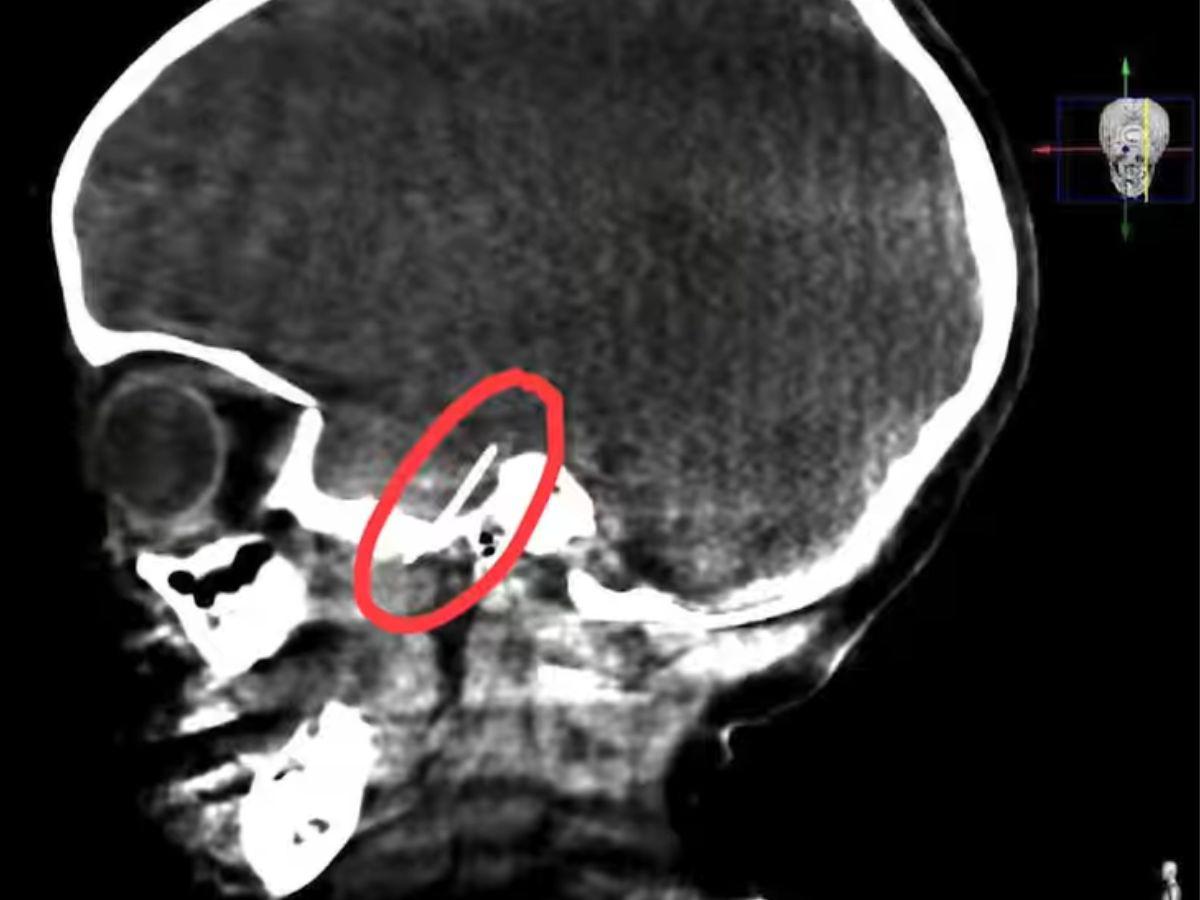

La radiografía que se le realizó a la menor mostraba la aguja incrustada.

Sin embargo, el procedimiento resultó más desafiante de lo esperado, ya que la aguja se había desplazado hacia el cerebro debido a los movimientos musculares. Esto obligó a los especialistas a realizar una incisión en el lado derecho de la cabeza de la niña para extraerla.

A pesar de la complejidad de la operación, los médicos lograron retirar la aguja con éxito, enfrentando el riesgo de dañar nervios o arterias durante el procedimiento.